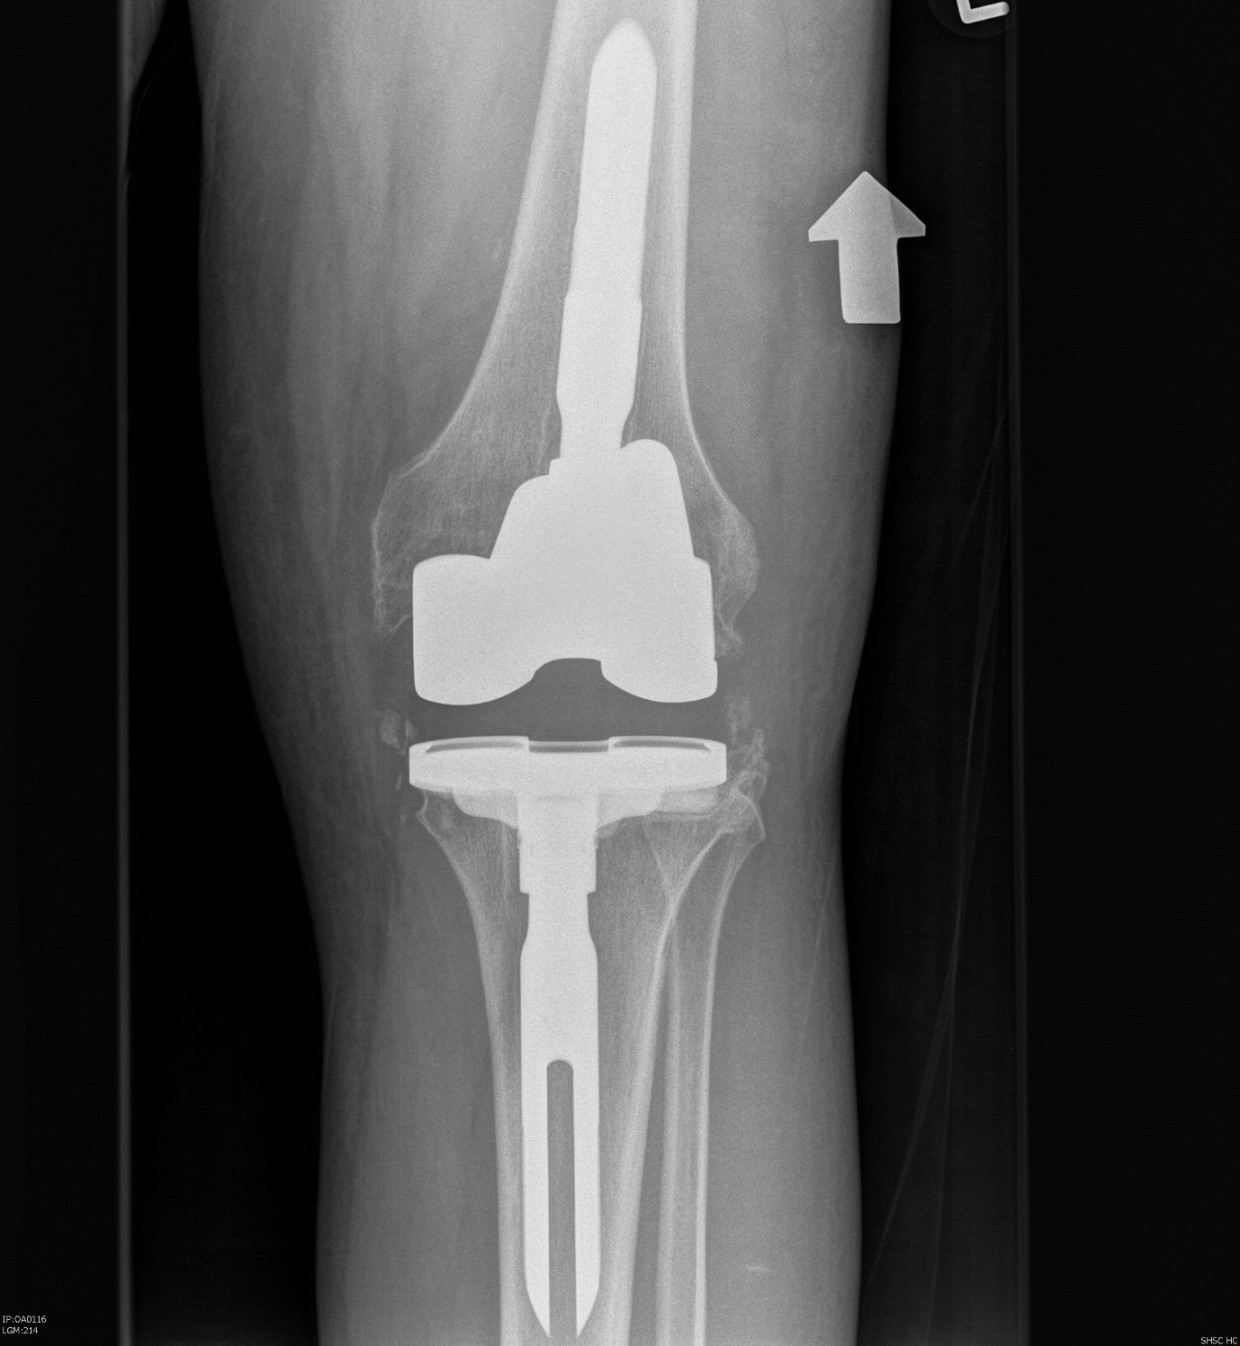

Prepare Tibia

Reason

- sets joint line

- enables flexion extension balancing

Insert trial intramedullary stem

Find IM canal

- ream until appropriate diameter

- desired length

- place trial

- set proximal cutting jigs off IM stem

Proximal tibial cut

Minimal tibial cut

- cut 1 - 2 mm off high side to preserve bone

- usually lateral side

- make resection for desired augment (5 or 10 mm) other condyle

- use jig

Insert trial tibia

Use offset as required

- ensures tibial component good fit on tibia

- tibial component not dependent on stem position

- ensure not internally rotated

- attach required augments

Recreate Joint line

Importance

- if rebuild tibial with augments and poly to correct joint line

- can rebuild distal and posterior femur to match

Markers

- scar from meniscal remnant

- 10 mm above fibula head

- 30 mm below medial epicondyle

- use templated distance from medial epicondyle on other knee

Restore joint line with appropriate sized poly